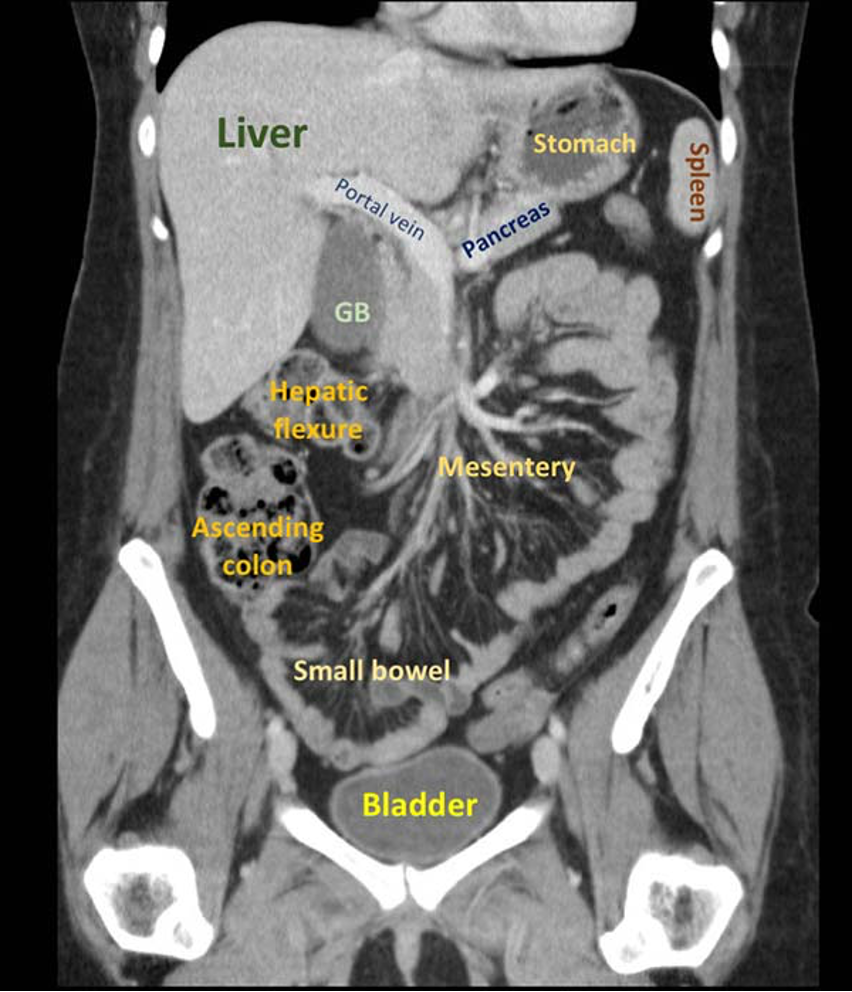

Nævn basale organer på CT:

A